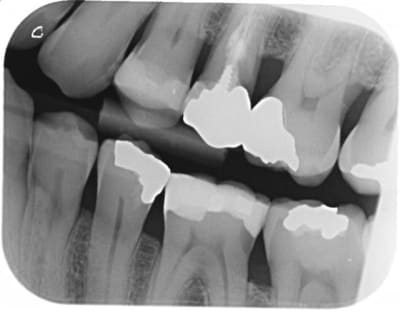

Je compare les btw precedents et tombe sur un hic au niveau de 36 en evolution depuis 2010.

Pour ce que je vois sur les radios, ces soins sont propres, mais pas exceptionnels. Notamment les faces proximales, reconstituées avec des matrices insuffisamment galbées qui produisent un point de contact presque occlusal et qui ne protège pas très bien l'espace inter dentaire en évitant aux aliments de se coincer.

Ceci étant, nous avons tous des patients qui ne passent pas assez les brossettes inter dentaires et déclenchent des caries cervicales incontrôlées.

je m'inquiéterais aussi pour la 25.

face distal de 23 également, y a une petite radio clarté.